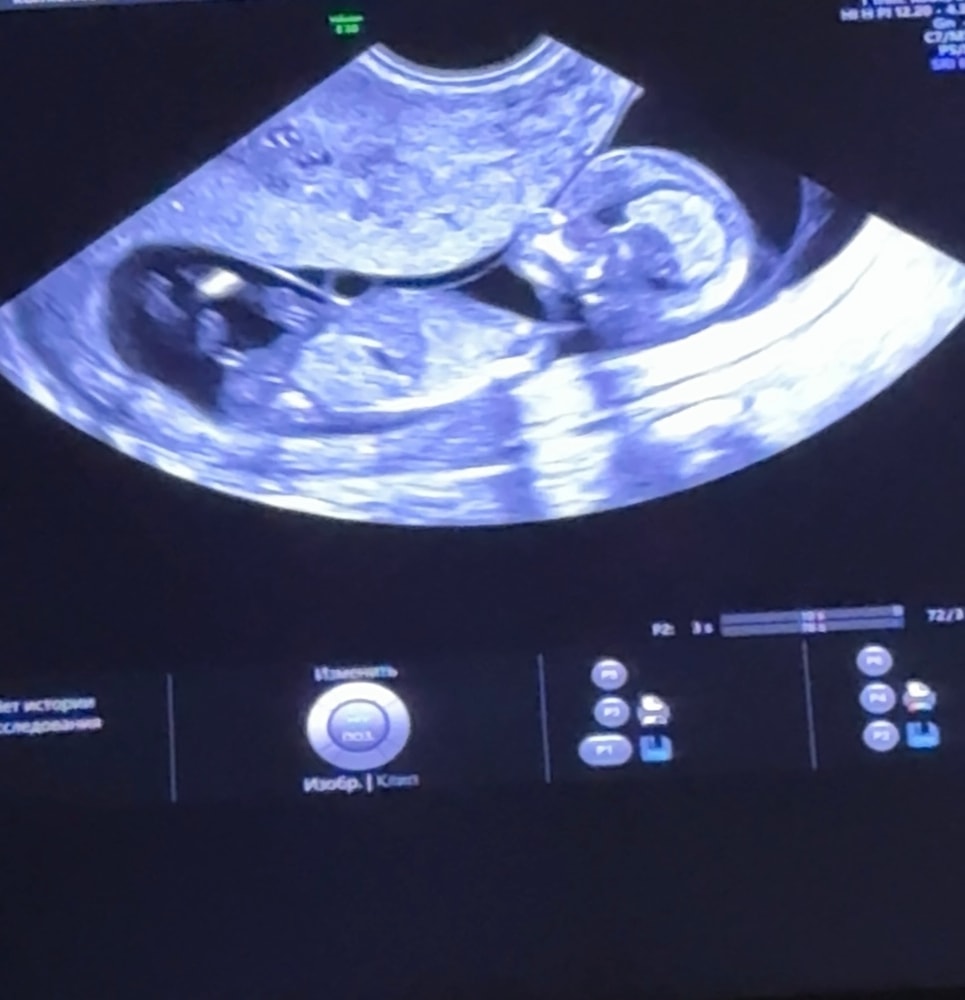

Первый скрининг. Как думаете мальчик или девочка?

Девочка, половой бугорок параллельно позвоночнику располагается

Да это ноги и пуповина похоже) По очертаниям ставлю на даму😁

Я вижу только ноги😃

Вам тонус не ставили? По снимку на мальчика поставлю

Если на фото бугорок, а не ножка, то мальчик.

Мальчик

Я тоже предполагаю девчонка))